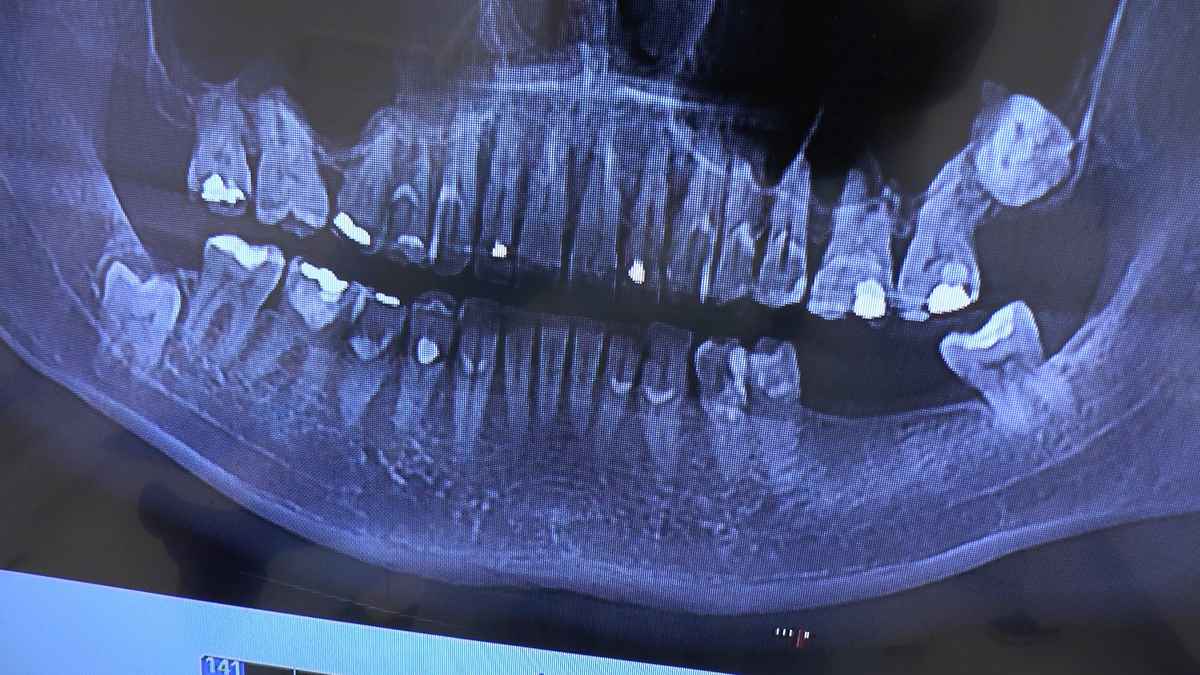

Właśnie trwa ostatnia przed wakacjami sesja szkolenia dla adeptów implantologii – Practiculum Implantologii. Jest bardzo intensywnie, wiele zabiegów, wiele o dużej skali trudności. Zabiegi pod kierunkiem Mentorów odbywają się na trzech stanowiskach. Przyjęto 15 Pacjentów.

W pierwszym dniu szkolący się lekarze wykonali kilkanaście zabiegów wprowadzając 25 implantów. Były to:

implantacje natychmiastowe wykonane bezpośrednio po ekstrakcji zębów z zastosowaniem augmentacji i fibryny bogatopłytkowej

mnogie implantacje w bezzębnych szczękach

implantacje w brakach częściowych

wyłuszczenie torbieli szczęki z resekcją 3 zębów i zastosowaniem regeneracji kości i fibryny bogatopłytkowej.